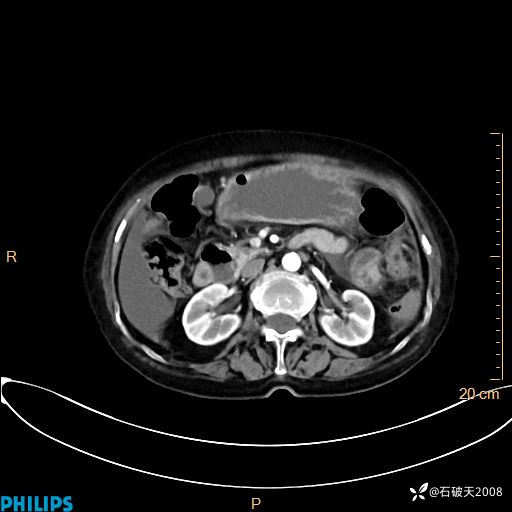

平扫